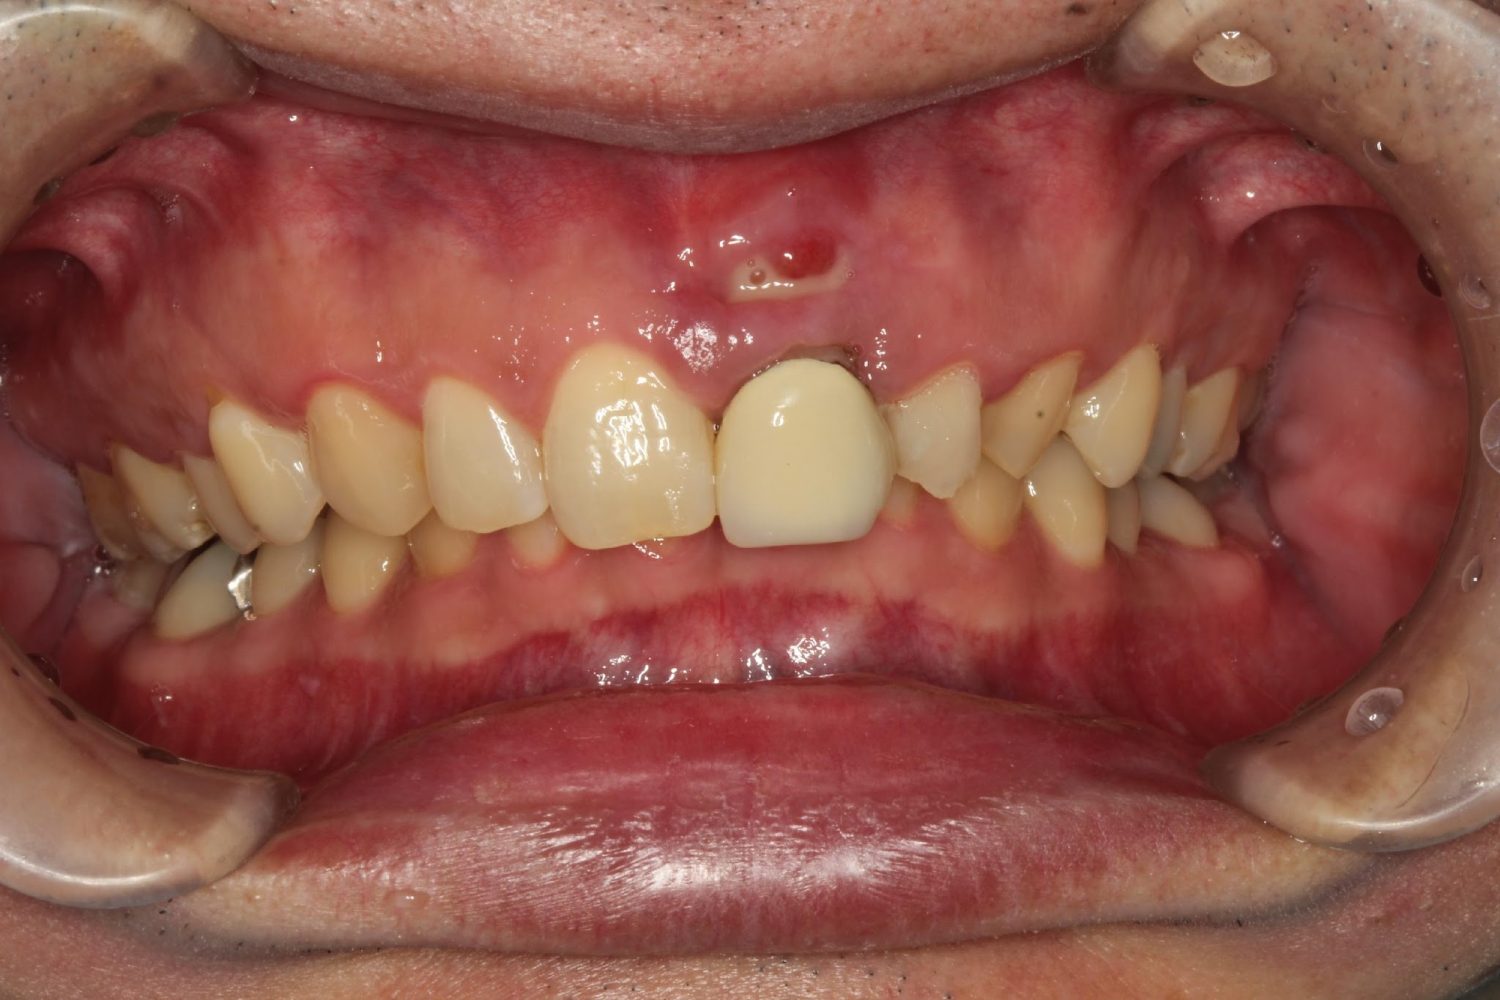

インプラント治療の症例紹介②

Before

After

主訴

前歯の脱落、歯肉の腫れ

治療内容

修復物の脱落時に支台築造のポスト部で歯質を破折。抜歯即時インプラント埋入をおこなったケース。

治療費

473,000 円(税込)

治療期間

8か月

治療回数

12回

想定されたリスク

※経年的な歯肉退縮の恐れ、インプラント周囲炎の恐れがありました。

残存した歯根に感染が少なく、抜歯時即時にインプラント埋入手術を行った。術後〇年経過し安定している状態。